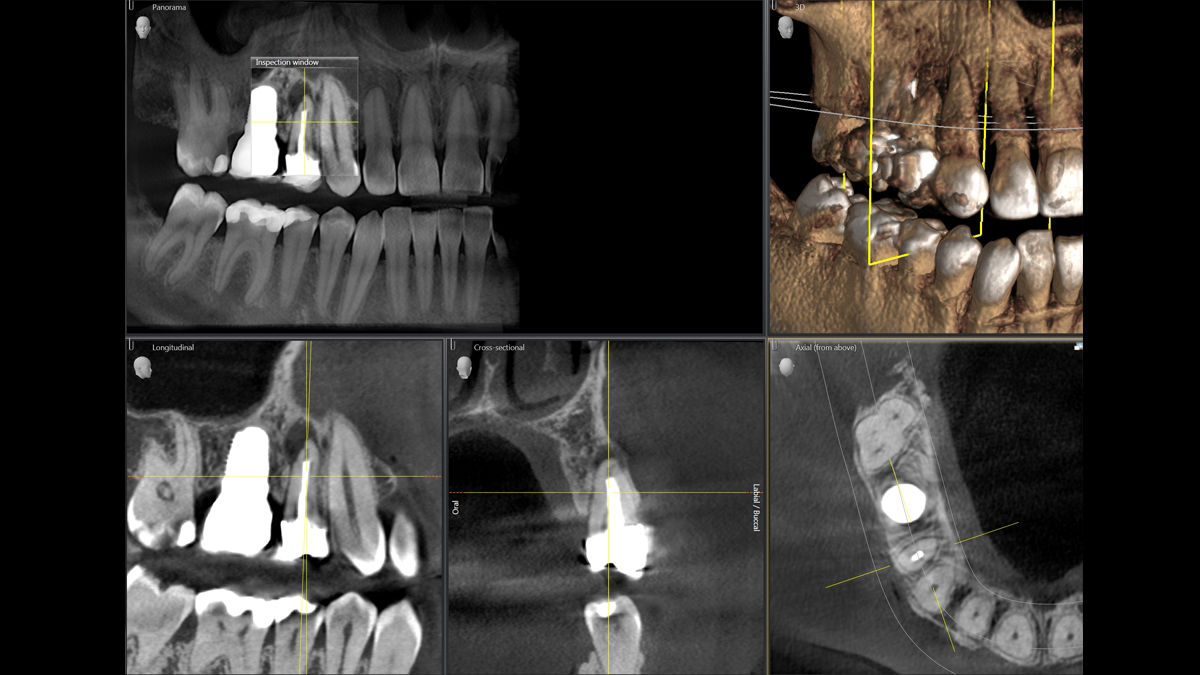

Modo de alta definición

Para determinadas indicaciones, por ejemplo, la visualización de los canales de raíces finas, el modo de alta definición (HD) muestra todos los detalles necesarios.